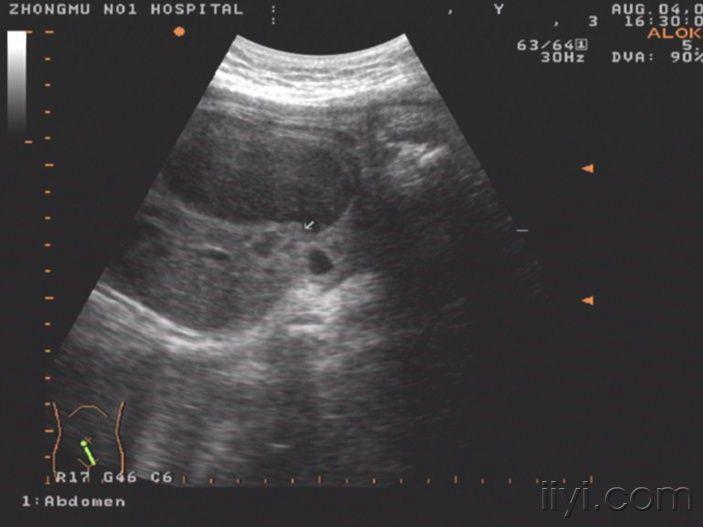

该患者肝脏在左侧,胃泡和脾脏以及小肠位于右侧.

你见过这么大的胎儿胃泡吗你考虑什么畸形

胃泡偏大,你们看得懂吗